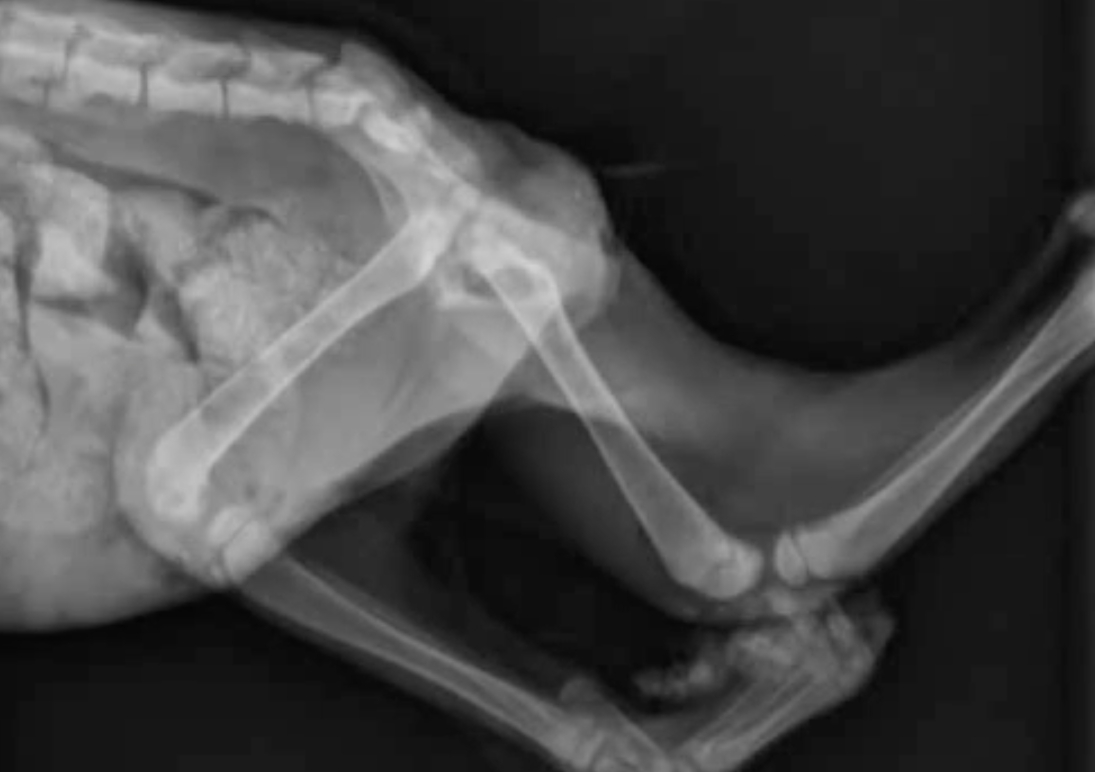

Hypoxia, hypoventilation, hypothermia, and hypotension are all complications associated with general anesthesia. Our discussion will cover the causes, complications, current solutions and treatment guidelines for these all too common complications of anesthesia in small animals.